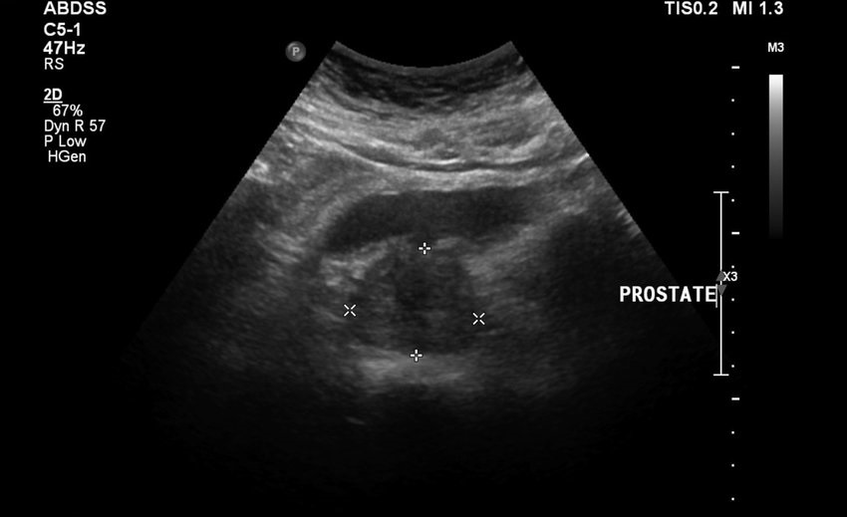

Ez zuten gomazko bizia lasai utzi, orduan bizkarreko mina gehitu zitzaien, probak eta ultrasoinuaren emaitzak txarrak ziren. Literalki ezinezkoa zen komunetik urruntzea, gerrikoa eta mina etengabea izan zen. Prostataren masaje zuzena preskribatu zen, eta horrek izua sartu ninduen. Sendatzeko beste metodo traumatiko gutxiago bilatzen hasi zen.